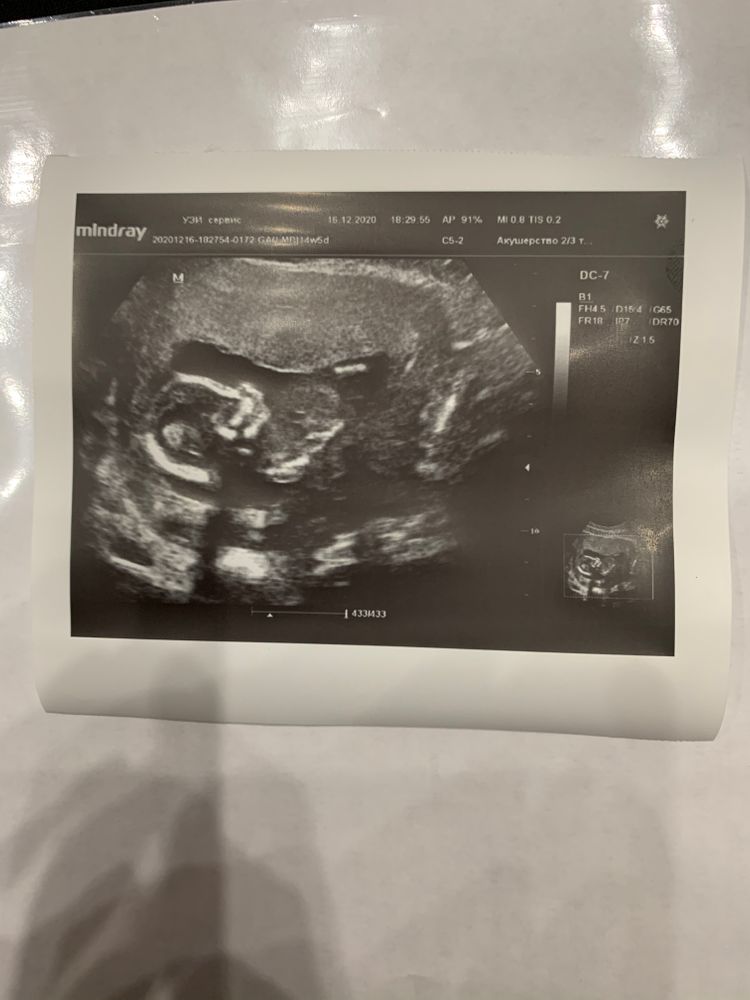

Мое чудо

УЗИ было на 14+5

Но по узи поставили 15+1 и сказали что скорей всего мальчик🥰